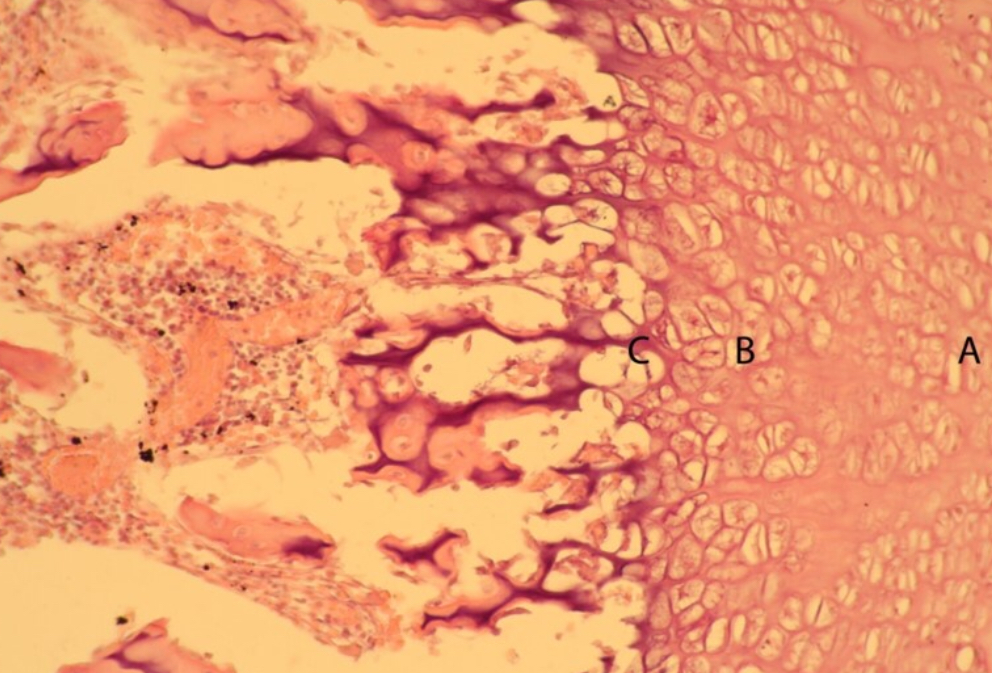

The following photomicrograph shows a portion of an epiphyseal plate. The specific region of the growth plate indicated by the letter “B” represents which of the following growth plate zones?

A. Calcification zone

B. Proliferative zone

C. Reserve zone

D. Hypertrophic zone

Identify the fine lines indicated by he letter “A”

A. Bile canaliculi

B. Haversian canaliculi

C. Elastic fibers

D. Collagen fibers

B. Haversian canalicul